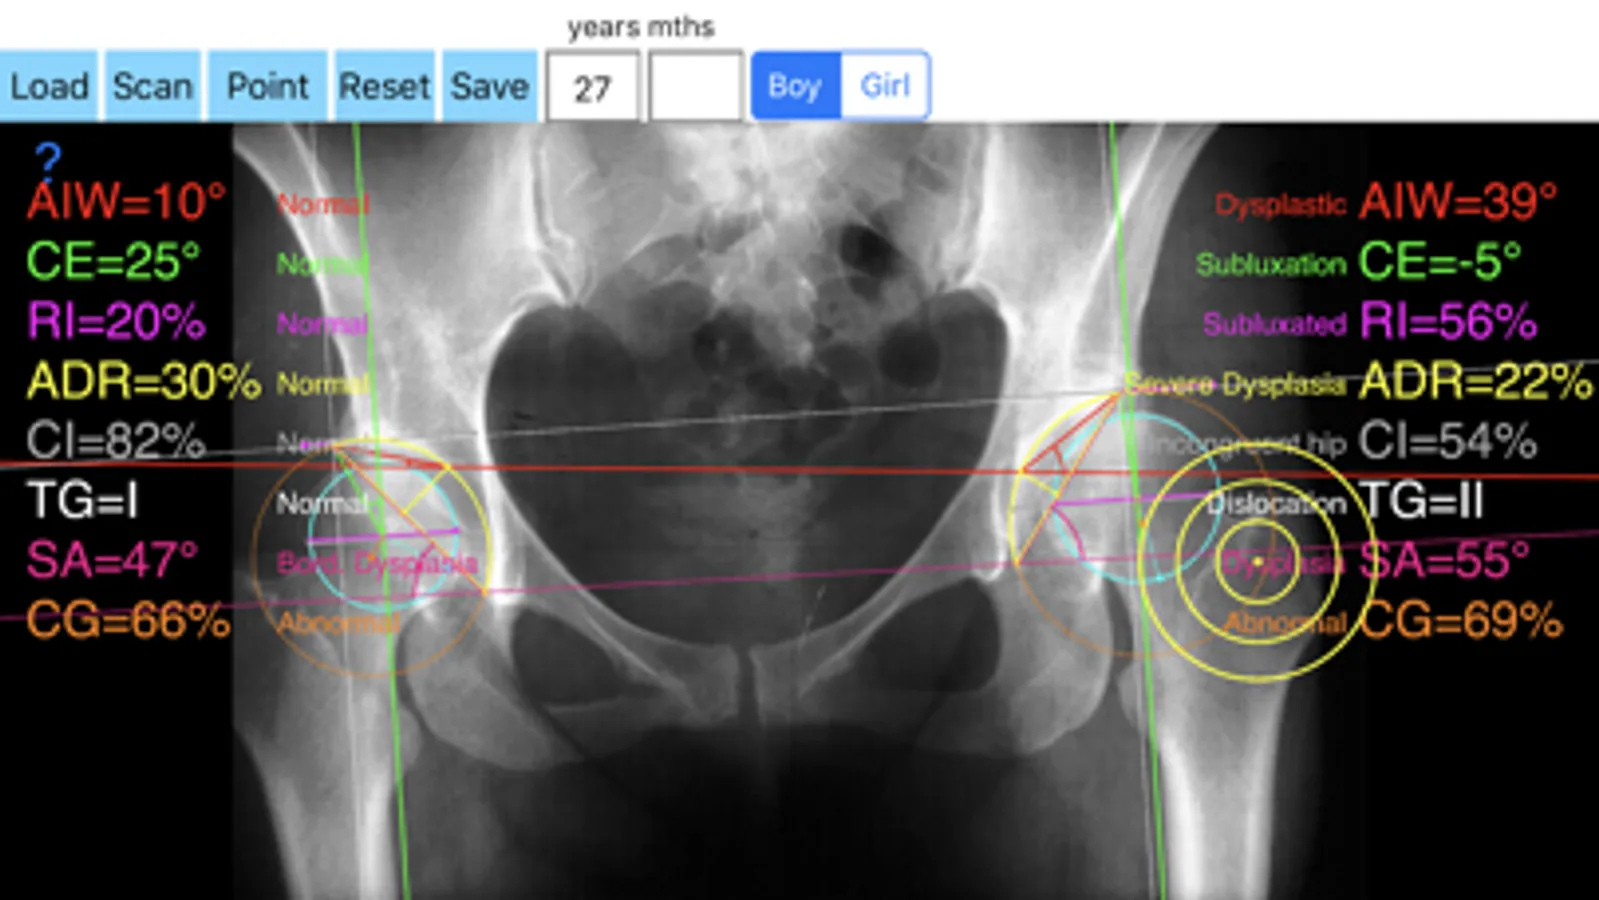

Hip dysplasia leads to premature osteoarthritis of the hip and accounts for many of total hip replacements in patients. The early diagnosis is extremely important and is based mainly on the radiological findings. In a radiographs correctly performed measurements of Indexes like the Acetabular Index (AI), the Center-Edge (CE), the Acetabular Depth-Width Ratio (ADR), the femoral head extrusion index or Reimer Index (RI), the Congruity Index (CI), the Sharp’s angle (SA), Tonnis grade of dislocation (TG), the Acetabular Index of the Weight-Bearing Zone (AIW) or Horizontal Toit externe angle (HTE), and Congruence Index (CG) are important for an the orthopaedic surgeon who wants objectively to asses and monitor optimally on standard radiographs the hips. These measurements usually performed in one X-ray by the traditional way which is time-consuming and cumbersome. We offer this new app, in which simply by marking five points at each hip you measure in an instant, all these indexes. The app also compares the results with normal age, gender and side specific reference databases retrieved from the international literature.

-Offers a very convenient way to determine the most accurate possibly way nine Indexes of hip dysplasia at once. By inserting the gender the age and marking five points at the same X-ray, at each hip, the App calculates the nine above mentioned indexes (AI, AIWB, CE, RI, ADR ,CI, SA,TG, CG) without to have to repeat each measurement separately. You measure all radiographic Indexes in one picture. Gender age and side-specific normal reference databases are used and in cases where values are out of normal ranges, the hips are categorized according the measured Index normal categorisation.

In a busy everyday practice, measuring in X-rays in clinical settings it is time consuming and cumbersome. Accessory instruments like protractors, goniometers, well sharp pencils, rulers or even transparent papers must be available. In case you have a packs system usually you don’t have the reference data. The app offers a very convenient and also accurate way to perform most common radiographic measurements for hip dysplasia, in a blink of an eye in front of your screen. The build in feature of the app, allows results to be compared and categorized according to gender, age and side-specific normal reference databases and help decide what could be considered normal or pathologic.